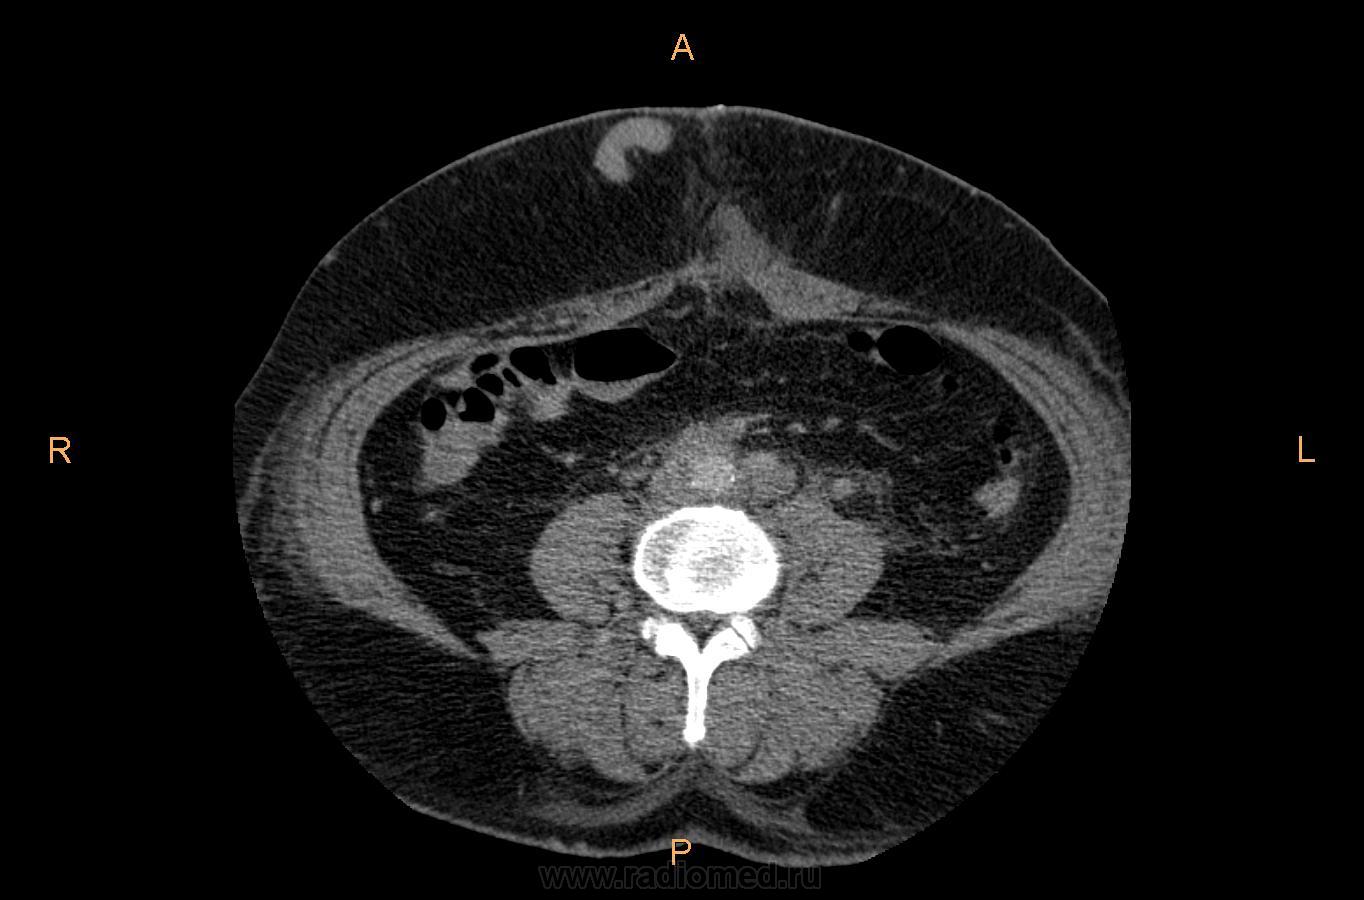

Пациент 56 лет, в последних числах июня месяца был прооперирован по поводу cr левой почки, спустя 2 недели после операции возникли боли в нижних конечностях и отечность голеней, при этом  отмечается набухание вен передней стенки живота. Данные жалобы перечислил ангиохирург, который обратился к нам повторно пересмотреть проведенное исследование.

МСКТ-органов брюшной полости от 21.06.2010г. до оперативного вмешательства:

МСКТ-органов брюшной полости от 26.07.10г. после оперативного вмешательства: